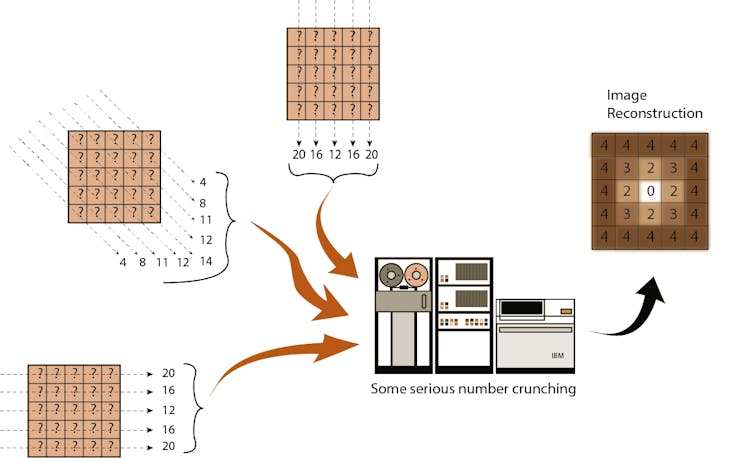

First, he would conceptually divide the brain into consecutive slices – like a loaf of bread. Then he planned to beam a series of X-rays through each layer, repeating this for each degree of a half-circle. The strength of each beam would be captured on the opposite side of the brain – with stronger beams indicating they’d traveled through less dense material.

Finally, in possibly his most ingenious invention, Hounsfield created an algorithm to reconstruct an image of the brain based on all these layers. By working backward and using one of the era’s fastest new computers, he could calculate the value for each little box of each brain layer. Eureka!

It was not a fast process – 30 minutes for the scan, a drive across town with the magnetic tapes, 2.5 hours processing the data on an EMI mainframe computer and capturing the image with a Polaroid camera before racing back to the hospital.